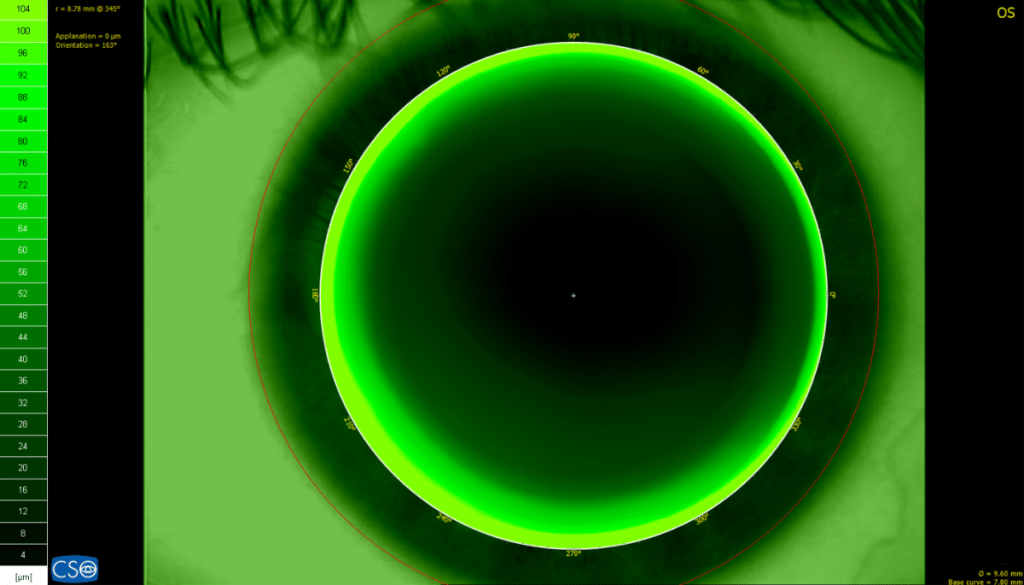

VIDEOKERATOSCOPE

Antares+ has white light to capture color images and videos as well as cobalt blue light for the analysis of contact lens fitting with fluorescein. The magnification can be changed allowing the capture of images with a wide visual field such as the tear meniscus and corneal redness.

CONTACT LENSES APPLICATION MODULE

A contact lens fitting module is available, which simulates the fit of rigid contact lenses based on an internal database of many lens manufacturers.